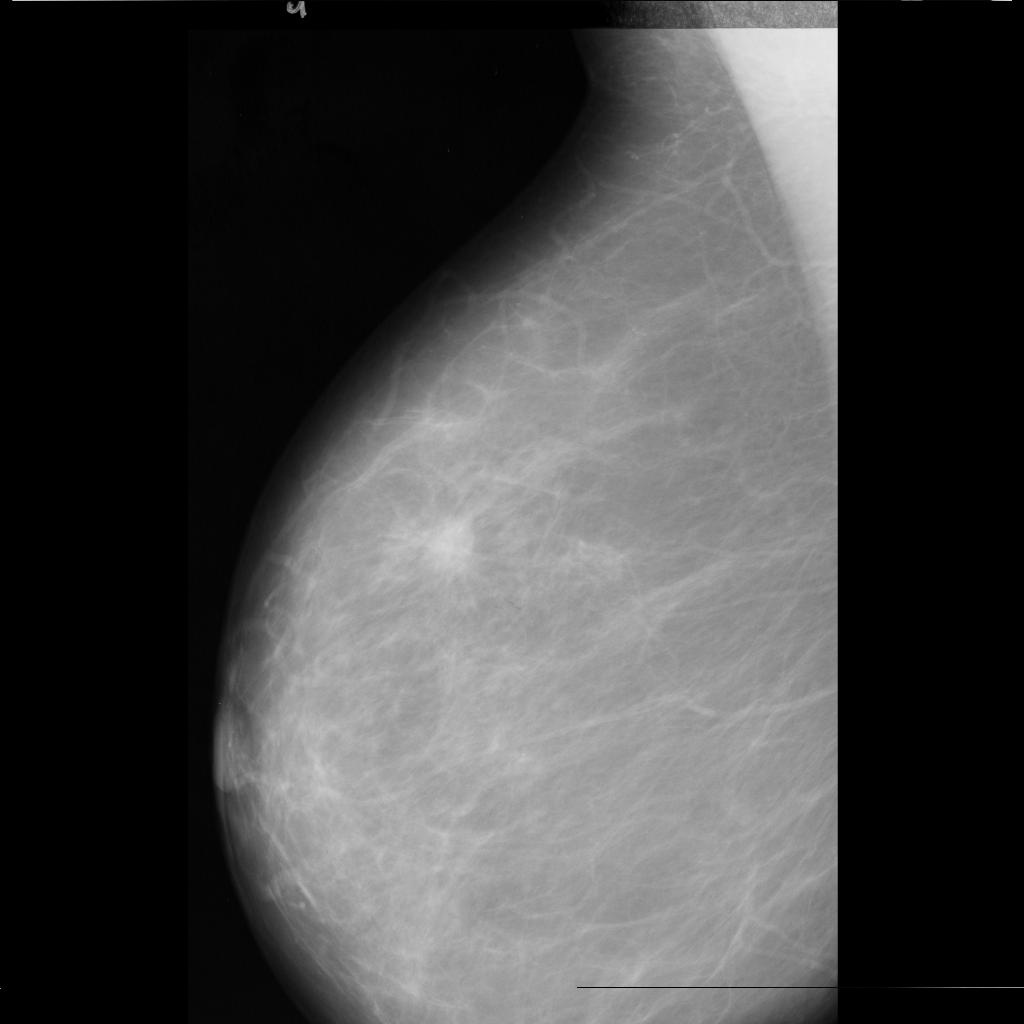

benign